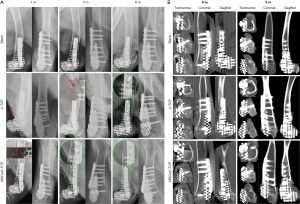

Evaluations of the bone defect repair

Repair of the bone defect in the lateral half of the goat’s distal femur

The previously made 5.3 cm-long bone defect in the goat’s lateral half of the distal femur and the matching Ti6Al4V frame filled with MSCs/β-TCP particles are shown in Figure 6. X-ray radiography showed that particles scattered on the edge of the frame were still seen in the pure β-TCP–filled group but not in the MSCs/β-TCP–filled group at 3 months after the operation. Also, the presence of bone hyperplasia at the proximal fracture site could be observed at 3 months after surgery in the MSCs/β-TCP–filled group, whereas a similar presence could be seen only at 6 months after surgery in the β-TCP–filled group. The X-ray radiography also confirmed a perfect match between the frame and defect (Figure 7A). CT could see tissue growth within the blank group frame, pure β-TCP–filled group, and MSCs/β-TCP–filled group at 6 and 9 months after surgery (Figure 7B).

The goat distal femur’s lateral half had both partial weight-bearing function and complex geometry and was easy to expose and observe. Therefore, it was used as a bone defect model in this study. Intraoperative photos and postoperative X-rays showed that the frame prepared by 3D printing completely matched the defect shape, and the shape was still well maintained 9 months after surgery. Postoperative X-ray radiograms showed that the scattered particles around the frame in the MSCs/β-TCP–the filled group had degraded and disappeared by 3 months after surgery, whereas those in the β-TCP–filled group were still visible at 3 months after surgery, suggesting that the former had a relatively faster degradation rate than that of the latter, which is consistent with the results found in our previous study (30). Also, the bony bridging presence at the proximal fracture site was seen earlier in the MSCs/β-TCP–filled group than in the β-TCP–filled group, which may have been related to the recruitment of autologous MSCs by implanted MSCs to promote local bone ingrowth (31,32). From the CT results, even though we rounded the frame’s distal end, there was still joint damage, such as patella displacement and joint wear. This finding may be because the end of the frame damaged the outer protective complex during the wear process. Therefore, it may be more appropriate for defects with joint retention to adopt a frame with a non-porous and polished surface. In terms of defect repair, the CT results showed that tissue ingrowth was present even in the frames without material filling, suggesting that a microporous structure may not be necessary for tissue ingrowth. Due to the interference by metal artifacts, we could not evaluate the tissue composition based on the tissue’s grey value within the frame.